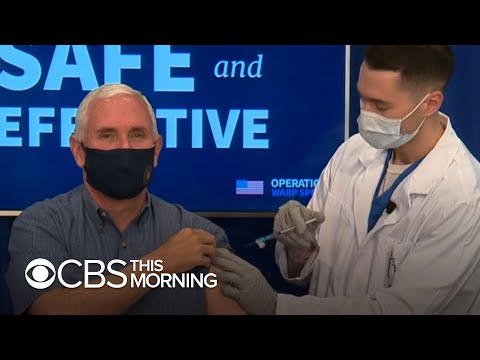

Vice President Mike Pence gets vaccinated on live TV

Pence calls the vaccine rollout the “beginning of the end of the pandemic.”

Vice President Mike Pence gets vaccinated on live TV

Vice President Pence, second lady get COVID-19 vaccine on live TV

Mike Pence Gets Covid-19 Vaccine at White House

US vice-president Mike Pence vaccinated for Covid: 'Important and symbolic'

US Vice President Mike Pence gets vaccinated | World News | WION News

Mike Pence gets vaccine as deaths top 3,000 for third day